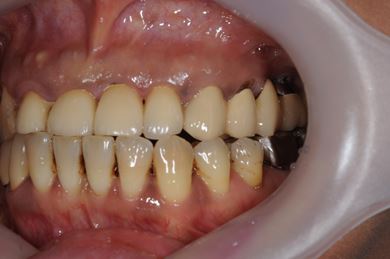

インプラントの症例写真 IMPLANT

抜歯即日スピードインプラント治療

| 性別/年齢 | 女性 / 44歳 | ||||||||||||||||||||||||||||||||

| 主訴 | 上のさし歯がグラグラする。インプラントにした方が良いのか、相談したい。 | ||||||||||||||||||||||||||||||||

| 治療方針 | 抜歯と同時にインプラントを埋入し、治療期間を短縮する。 | ||||||||||||||||||||||||||||||||

| 治療内容 | インプラント2本(抜歯即日スピードインプラント)、メタルボンドセラミック2本 | ||||||||||||||||||||||||||||||||

| 総治療費 | 458,588円 | ||||||||||||||||||||||||||||||||

| 治療期間 | 6ヶ月 |